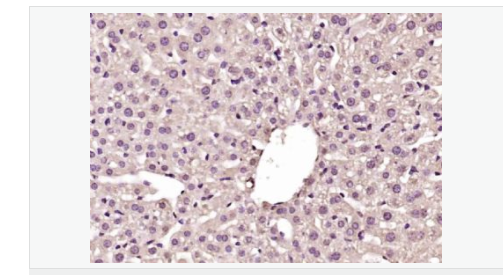

| 產(chǎn)品應(yīng)用 | WB=1:500-2000 ELISA=1:5000-10000 IHC-P=1:100-500 IHC-F=1:100-500 IF=1:100-500 (石蠟切片需做抗原修復) not yet tested in other applications. optimal dilutions/concentrations should be determined by the end user. |